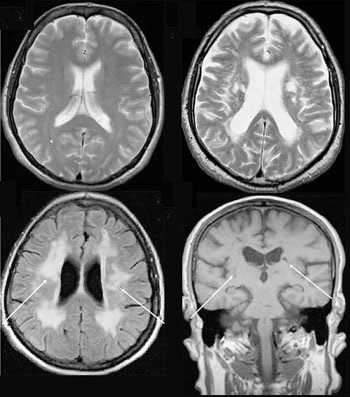

Что показывает МРТ

Магнитно-резонансная томография или МРТ - это сфокусированный метод, который проводит очень детальное обследование. Диагностическая точность МРТ превышает УЗИ и во многих случаях КТ, за исключением сканирования полых органов (легких, желудка, кишечника) и костей. МРТ является золотым стандартом диагностики:

В отличие от быстрого КТ и УЗИ, магнитно-резонансное обследование требует времени - в среднем пациенту нужно лежать в томографе и соблюдать неподвижность 30-60 минут.

Принцип работы МРТ основан на эффекте ядерного магнитного резонанса. МР томограф в своей конструкции имеет мощный магнит, который создает магнитное поле, и датчик, который подает радиочастотные сигналы. В такой ситуации протоны атомов водорода начинают колебательные движения, выделяя при этом импульсы. Их улавливает компьютер томографа и преобразовывает в трехмерные изображения. Чем больше воды содержится в клетках ткани, тем детальней получается ее изображение. Поэтому на МРТ хорошо отображаются органы с большим содержанием воды: МРТ головного мозга, МРТ спинного мозга, МРТ глазных орбит, МРТ органов малого таза, МРТ позвоночника, МРТ суставов, и плохо визуализируются органы с большим содержанием воздуха МРТ органов грудной клетки или кости.

Основы преимуществом МРТ перед КТ и рентгеном является отсутствие в ходе сканирования какого-либо излучения. А вот недостатком этого метода диагностики будет ряд ограничений - наличие ферромагнитного металла в теле пациента и имплантированных в организм водителей ритма, несовместимых с МРТ.

Магнитно-резонансная томография

В основе МРТ лежит явление магнитного резонанса, основанного на переизлучении радиоволн, взаимодействующих с атомами водорода, в избытке содержащимися в организме человека. Эти переизлученные электромагнитные волны улавливаются датчиком МР-томографа, усиливаются и в виде цифровых изображений появляются на экране монитора. Это безвредный и абсолютно безопасный для здоровья человека метод лучевой диагностики, так как в основе получения изображения отсутствует рентгеновское излучение, поэтому МРТ можно проходить неограниченное количество раз, с любым интервалом.

Существенное преимущество МР-томографии перед КТ заключается в том, что она не противопоказана беременным во II и III триместре и совершенно безопасна для детей. В МРТ исследуемая область сканируется в трех проекциях, что позволяет врачу-рентгенологу в полной мере оценить состояние тканей и органов исследуемой области, а высокая контрастность изображения и пространственное разрешение позволяют визуализировать серое и белое вещество головного мозга, оценивать состояние костного мозга и мягких тканей различной локализации. Кроме того, метод МРТ позволяет получать изображения сосудов головного мозга и сосудов шеи без введения контрастного препарата.

Конечно, как и многие другие методы исследования, МР-томография имеет ряд противопоказаний. Однако, если внимательно ознакомиться с ними, можно заметить, что в основном они связаны с наличием металлсодержащих имплантов (не обладающие магнитными свойствами устройства противопоказанием не являются), а также с выраженной клаустрофобией. Таким образом, в большинстве случаев МРТ может стать наиболее оптимальной и совершенно безопасной альтернативой компьютерной томографии и рентгенографии.